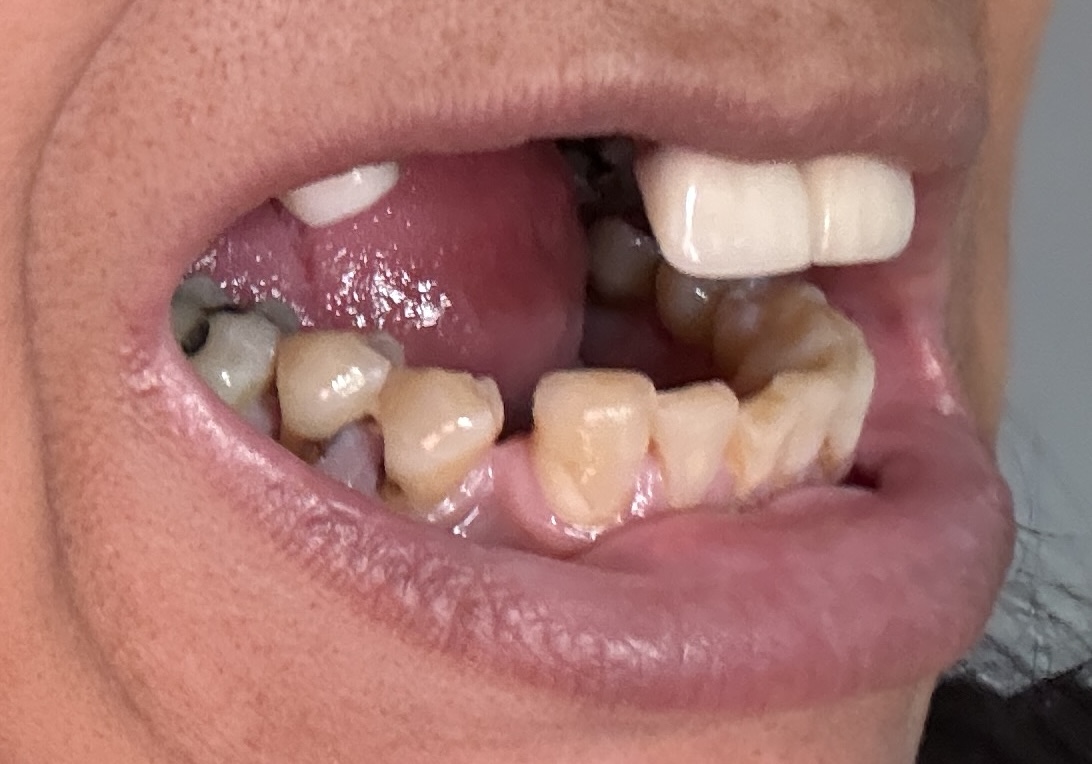

12,13,14 have had root canals in past and now have quite a bit movement. 2-5 have all had root canals in past and now the crowns are breaking down.

Overall information (lower arch)

Overall, all of my gums have receded and most of the bottom teeth are exposed w/ some roots and there are many cavities.